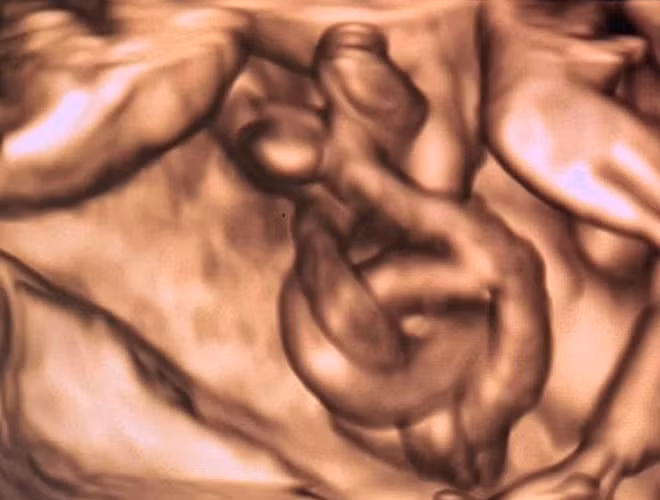

Hình ảnh dây nhau xoắn thắt nút qua siêu âm. Ảnh: BVCC

Ở tuần thai thứ 14, kết quả siêu âm thăm khám cho thấy song thai bị dây rốn xoắn quấn nhiều vòng, nguy cơ tử vong cho thai nhi trên 50%, tính mạng cả 2 thai nhi bị đe dọa từng giờ.

Tuy nhiên, ở tuần thai thứ 18-19, khi siêu âm, bác sĩ lại phát hiện thai phụ bị nhau tiền đạo, nhau cài răng lược. Đây là tình trạng nhau không bám ở vùng đáy tử cung như thông thường, mà một phần hay toàn bộ bánh nhau bám vào ở đoạn eo tử cung. Đây là một trong những nguyên nhân gây chảy máu trong 3 tháng cuối của thai kỳ và gây băng huyết nặng sau sinh.